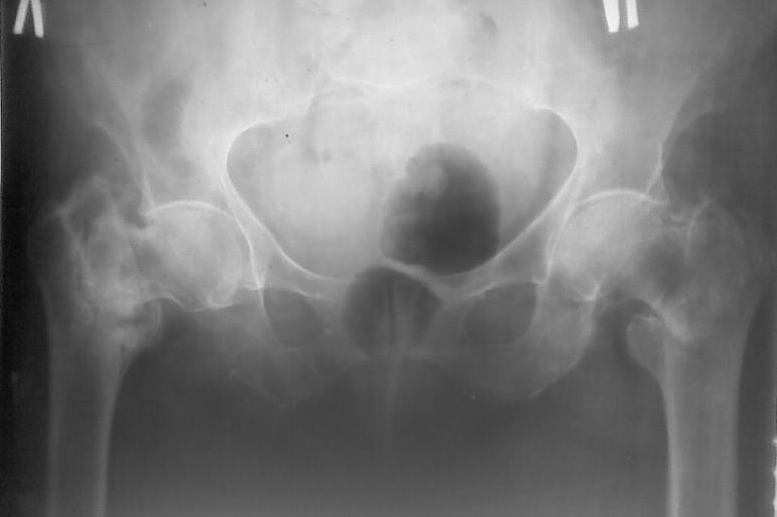

Поступила больная 80 лет, справа перелом свежий, слева - 4 летней давности.

Здравствуйте,уважаемые коллеги! Поступила больная 80 лет, справа перелом свежий, слева - нелеченный перелом 4х-летней давности. Больная проживает в частном доме, до последней травмы передвигалась с костылями, себя обслуживала.Соматически сохранна.

Помогите выбрать оптимальную тактику лечения (Гамма недоступна)

Наши варианты :

1. Справа DHS, слева - МВО, промежуток между операциями - 10 -12 суток

2. Справа DHS , слева - не трогать3. Справа DHS . слева протез Мура после скелетного вытяжения (?)

Я больше склоняюсь к третьему варианту,поскольку установка протеза позволит максимально быстро поднять больную.